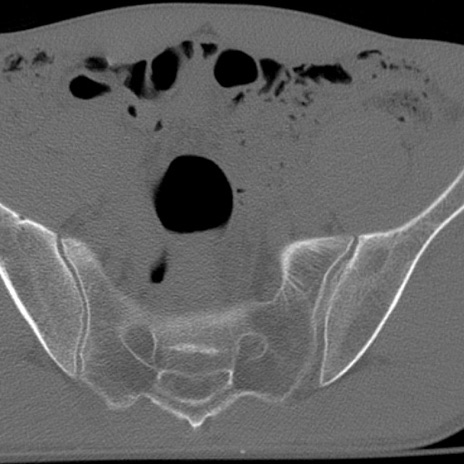

症例3 腰椎CT(横断像)

腰椎CT